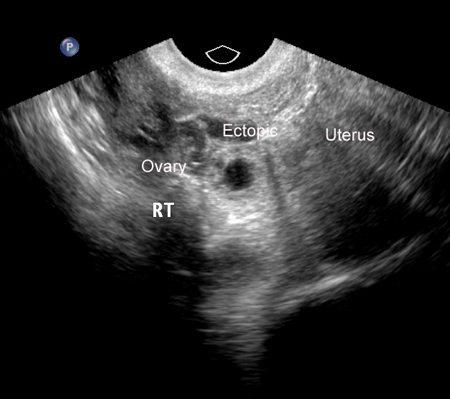

An ectopic pregnancy can be definitively diagnosed via ultrasound when a gestational sac with a yolk sac, or embryo, or both, is noted in the adnexa.[47] Not all ectopic pregnancies can be visualised on ultrasound; however, with increasingly high-resolution ultrasound and expert sonography, studies have shown that TVUS is both highly sensitive and specific in the diagnosis of ectopic pregnancy. However, there remains a significant proportion of cases (between 5% and 42%) where neither an intrauterine nor an ectopic pregnancy can be visualised on ultrasound. In these cases, the descriptive term pregnancy of unknown location (PUL) is used.[48][49][Figure caption and citation for the preceding image starts]: Ultrasound image of ectopic pregnancyFrom the collection of Dr Melissa Fries; used with permission [Citation ends].

[Figure caption and citation for the preceding image starts]: Ultrasound image of ectopic pregnancyFrom the collection of Dr Melissa Fries; used with permission [Citation ends].